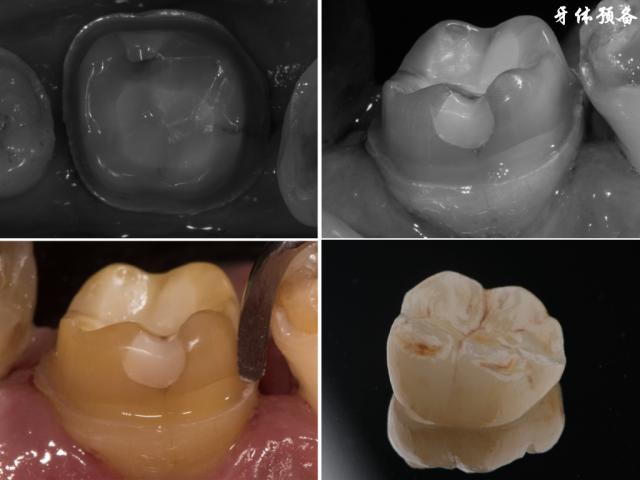

⚙️ 3. 牙体预备(核心步骤)

🪥 a. 唇侧预备(最关键的美学区域)

- 目的: 为瓷层提供足够空间(通常1.0-1.5mm),恢复牙冠的突度、形态和颜色。

- 方法:

- 肩台预备: 在龈上或平龈处预备一个连续、光滑、宽度均匀(通常0.8-1.0mm)的凹形肩台,肩台边缘应清晰、直角或135°内角,位于釉质内,避免在牙龈下方形成过深的凹槽。

- 聚合度: 从肩台向切端方向,预备体应有一定的聚合度(通常6°左右),便于就位和脱模,但不宜过大影响固位。

- 形态: 使用金刚砂车针(如圆头、火焰状)按照设计好的牙冠形态进行预备,去除足够的牙体组织,确保瓷层厚度均匀一致,避免过薄区域,注意恢复原有的唇面弧度和突度。

🧪 e. 精修与抛光

- 目的: 消除所有线角、锐边,使预备体表面光滑连续,便于印模和粘接。

- 使用细粒度的金刚砂车针或抛光车针,仔细修整肩台、线角、邻面、舌侧等所有区域。

- 确保所有边缘清晰、连续、光滑。

- 检查聚合度,必要时调整。

- 预备体表面应无倒凹、无粗糙面。